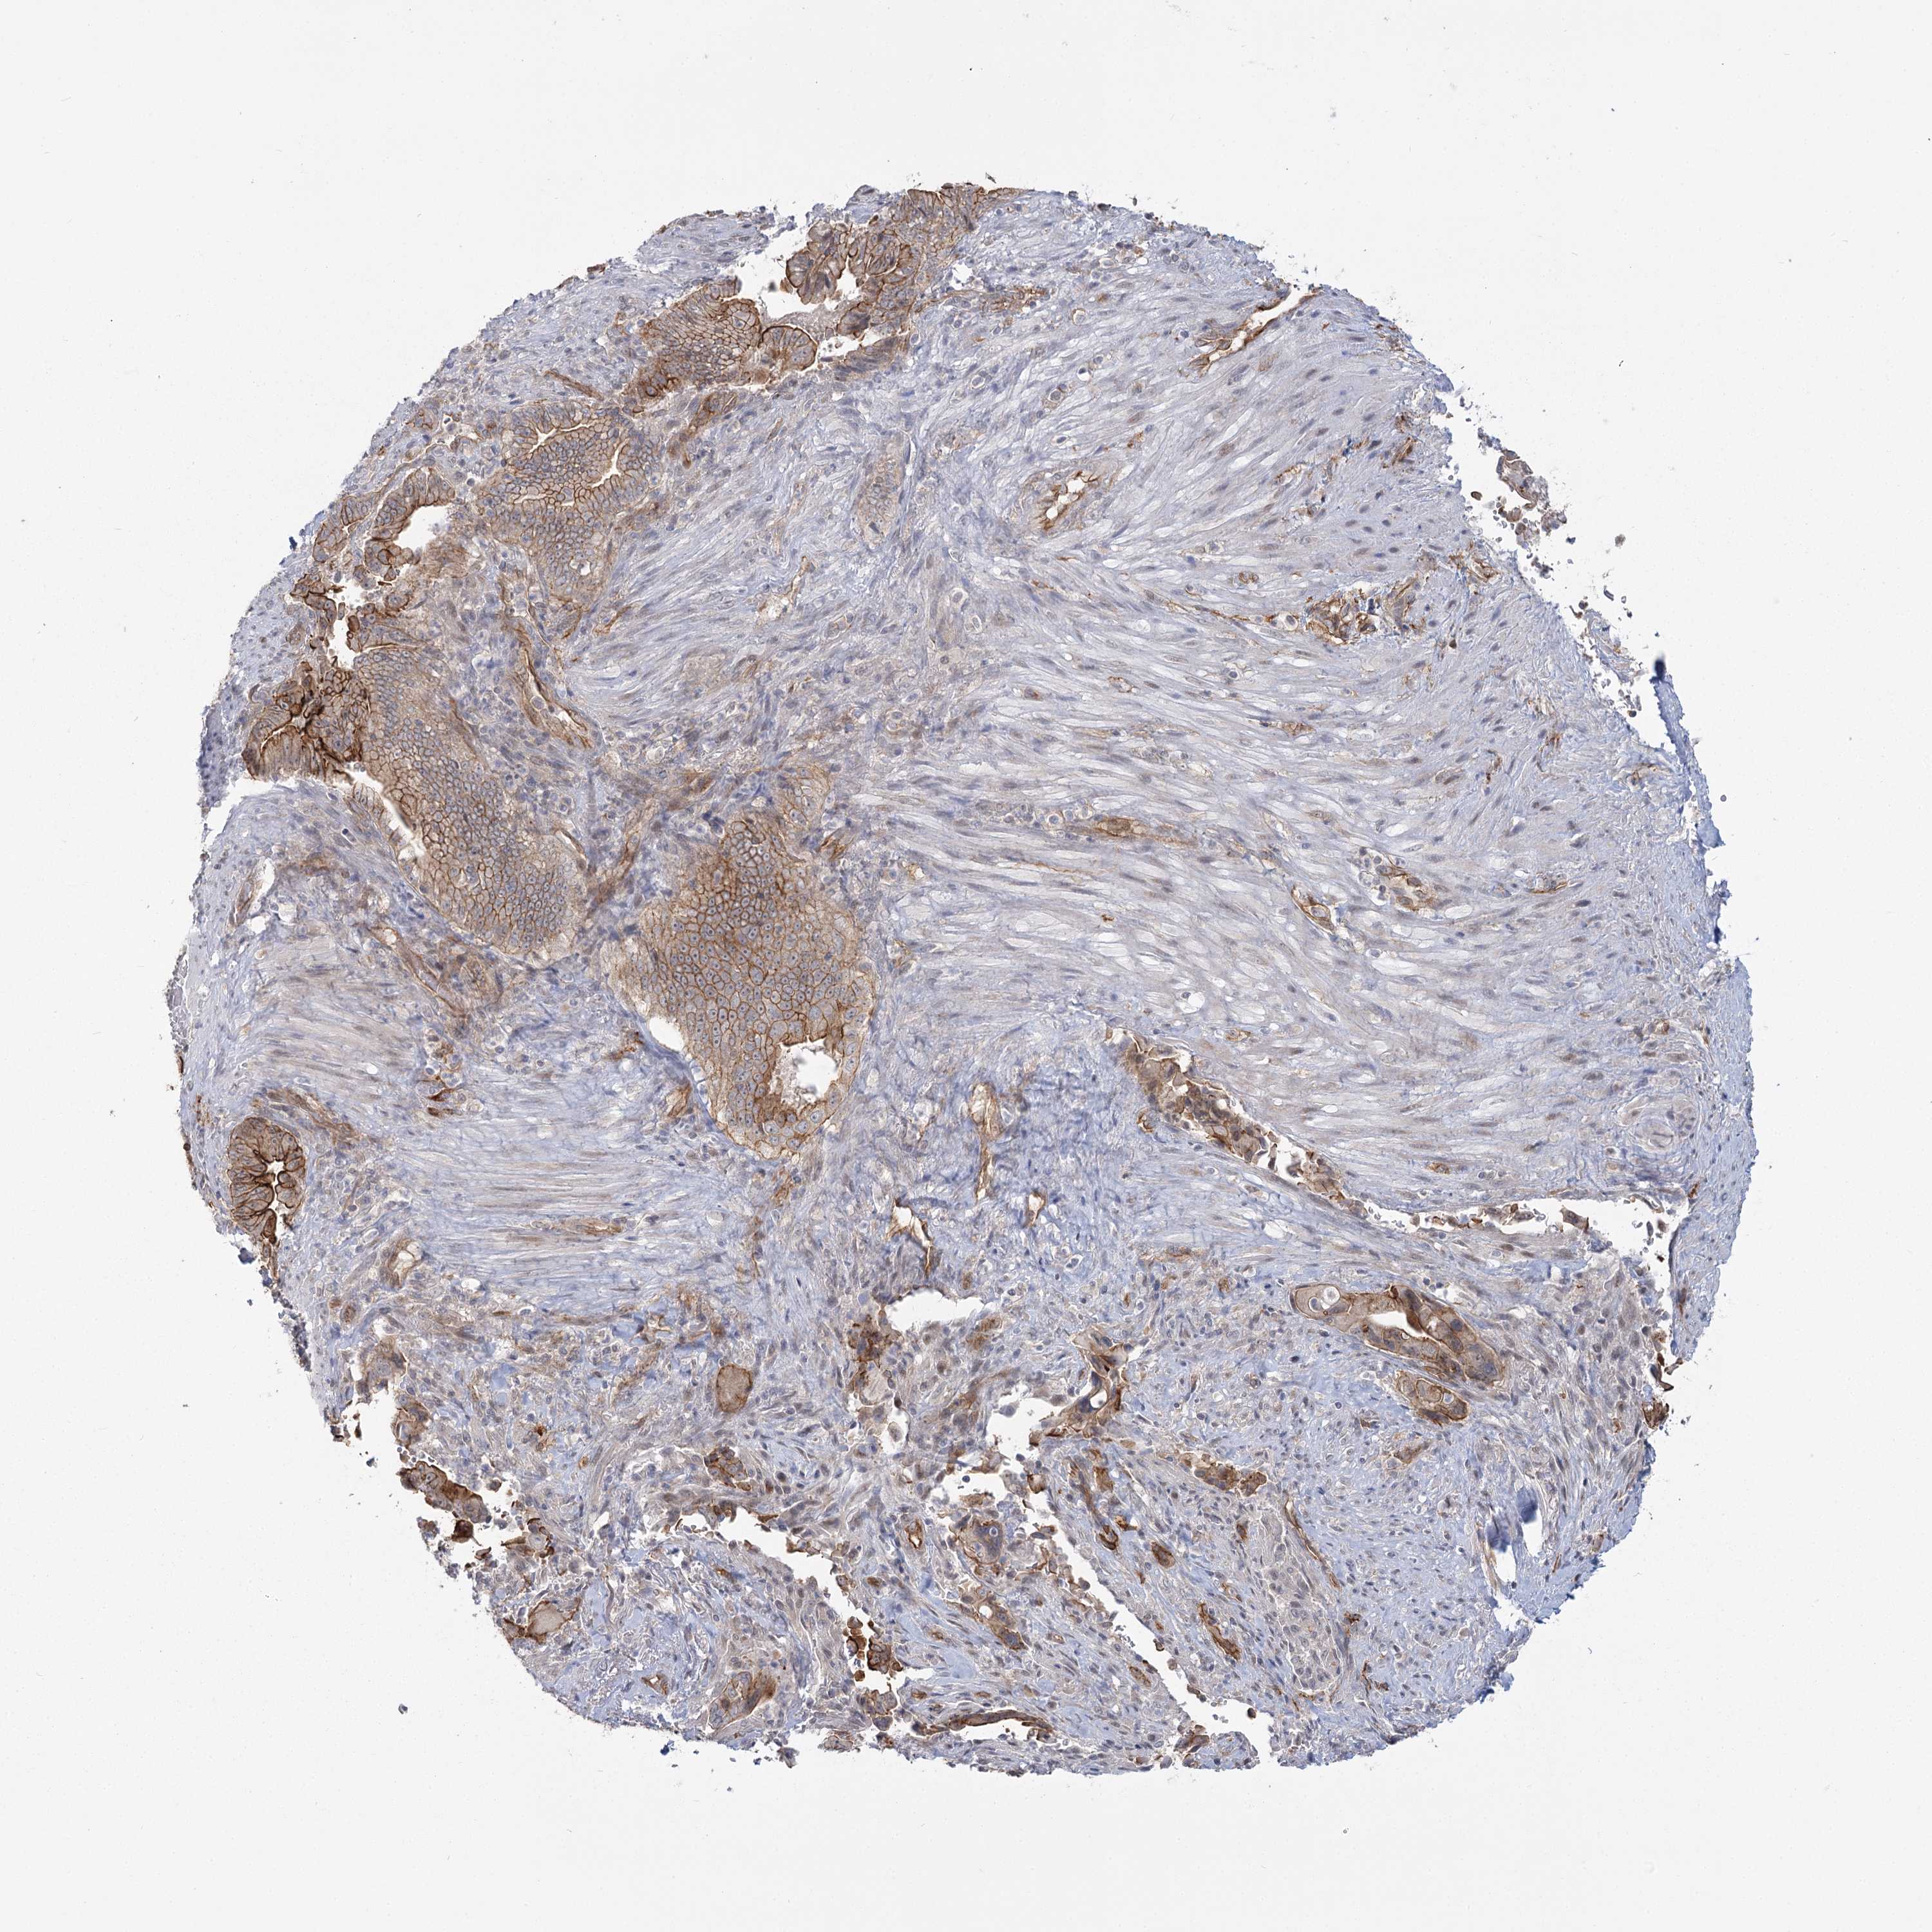

PANCREATIC CANCER - Protein expressioni

A mouse-over function shows sample information and annotation data. Click on an image to view it in a full screen mode. Samples can be filtered based on level of antibody staining by selecting one or several of the following categories: high, medium, low and not detected. The assay and annotation is described here.

Note that samples used for immunohistochemistry by the Human Protein Atlas do not correspond to samples in the TCGA dataset.

Antibody stainingi

Antibody staining in the annotated cell types in the current human tissue is reported as not detected, low, medium, or high, based on conventional immunohistochemistry profiling in selected tissues. This score is based on the combination of the staining intensity and fraction of stained cells.

Each image is clickable and will lead to virtual microscopy that enables deeper exploration of all samples and also displays staining intensity scores, fraction scores and subcellular localization as well as patient and tissue information for each sample.

Antibody HPA036194

Staining

High

Medium

Low

Not detected

Intensity

Strong

Moderate

Weak

Negative

Quantity

>75%

75%-25%

<25%

None

Location

Nuclear

Cytoplasmic/membranous

Cytoplasmic/membranous,nuclear

Adenocarcinoma, NOS